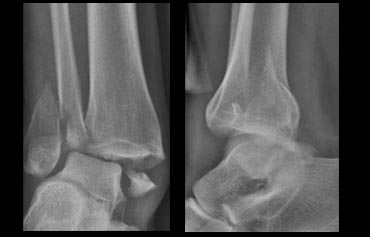

Weber A - stage 2 Weber A - stage 2

Stage 2

Stage 2 is uncommon and easy to detect.

More adduction force results in the medial malleolus being pushed off in a vertical or oblique way.

Stage 2 is unstable because the ring of the ankle is broken in two places.

Notice the horizontal orientation of the lateral malleolus fracture and the vertical orientation of the fracture of the medial malleolus.

Enormous forces must have pushed off the medial malleolus.